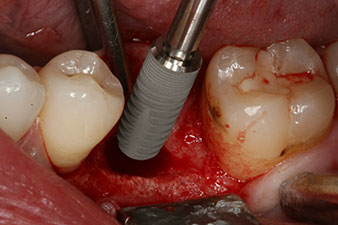

Implantat

Fig. 3: After preparation with the Implantmed implantology motor, an implant (diameter 4 mm, length 12 mm) was screwed in by the motor at a torque of 43 Ncm.

The implant was placed as planned after thorough removal of the granulation tissue (blueSky, bredent).

SmartPeg

Fig. 4: SmartPeg measuring posts screwed on to measure the implant stability quotients with the integrated W&H Osstell ISQ module.

The torque used for the machine-driven placement was 43 Ncm. In addition, after screwing a measuring post (SmartPeg) specially matched to the implant, the ISQ value was measured with the probe of the W&H Osstell ISQ module.